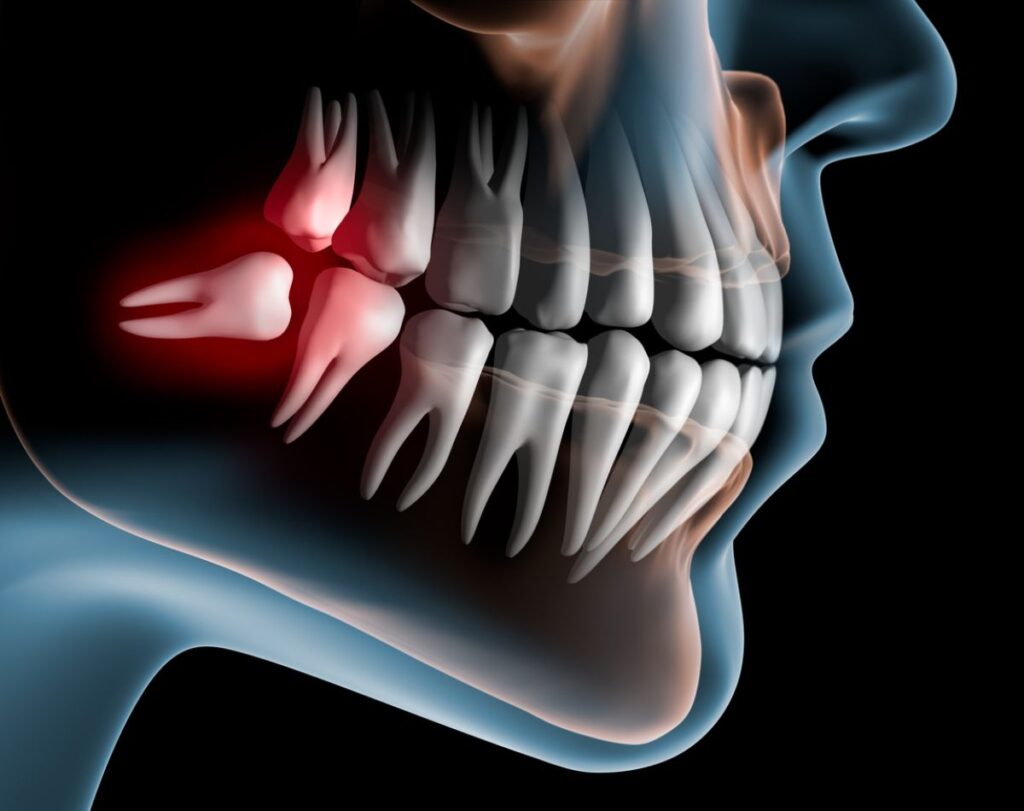

- Răng khôn mọc ngầm

- Toàn bộ răng nằm trong xương hàm, có thể đâm ngang hoặc chèn vào răng số 7 bên cạnh.

- Tại YEN DENTAL, khách hàng sẽ được chụp phim CT Cone Beam 3D để xác định chính xác vị trí và kế hoạch nhổ răng an toàn.